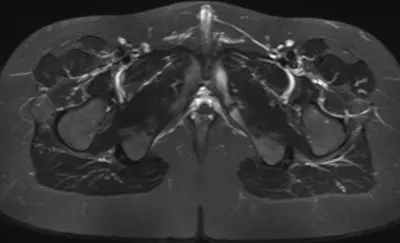

Ischiofemoral impingement

MRIPelvisAxial+1

4/23/2026